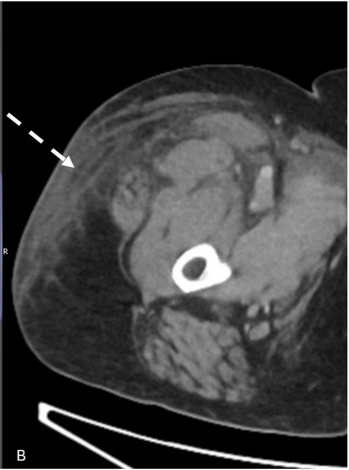

A. CT显示IVC(白色箭头)中血栓的近端范围, |

B. 右下肢浅表水肿(虚线箭头) |